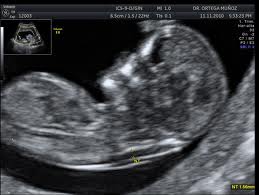

Ecografía. La ecografía es el método de exploración imprescindible en el ámbito del diagnóstico prenatal. Tiene unos momentos clave de aplicación:

En el segundo trimestre. Especialmente alrededor de la semana 20, es la época más adecuada para el diagnóstico de la mayoría de malformaciones de tipo anatómico. Debe practicarse por personal especialmente cualificado, preparado y acreditado para este tipo de ecografías. Igualmente se requieren equipos eccográficos de alta definición, dotados de tecnología como el Doppler Color y la Tridimensión, que nos permiten descubrir detalles muy precisos de toda la anatomía fetal.